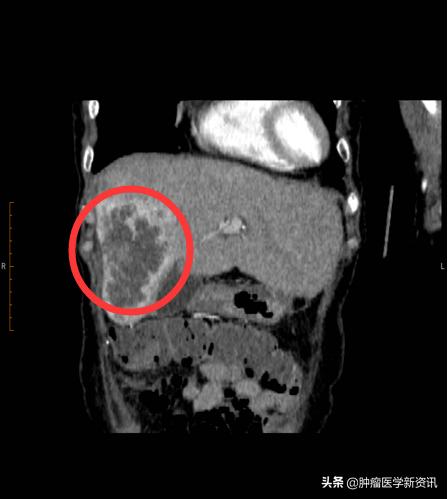

原本以为母亲的病情稳定了,不料,打击接踵而来。2019年9月,复查结果显示肝右叶占位,发生肝转移,双肾多发小那囊肿同前,肿瘤标志物CEA>500,CYFRA21-1上升到了15.27,CA19-9>800,CA242>500,CA72-4>250,NSE为40.31,病情发生恶化。一向坚强的王女士母亲,开始变得疑虑焦躁。11月,主治医生建议使用贝伐单抗+奥沙利铂化疗,病灶缩小后进行手术。这意味着,王女士的母亲需要继续新一轮的化疗和手术,继续承受治疗带来的身心痛苦。这一次,王女士拒绝了,她说我真的不忍心看母亲再受折磨了。

治疗前

2020年3月,王女士母亲在持续进行2次iNKT癌症免疫治疗+肝部介入后,2个月的时间,王女士的母亲肝部10cm肿瘤缩小了1/3,肿瘤标志物降落接近一半,精神也越来越好,就连吃饭都比之前好多了,可以如正常人般生活了。

治疗后